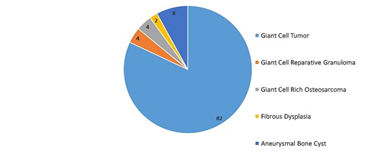

Result & conclusion: Common lesions under this category were Giant Cell Tumour of Bone (41), Aneurysmal Bone Cyst (04), Giant Cell-Rich Osteosarcoma (02), Giant Cell Reparative Granuloma (02), and Fibrous Dysplasia (01). Detailed Histopathological study and clinic-radiological correlation is very helpful to arrive at precise and accurate diagnosis. This in turn, is very helpful for precise treatment of these patients and to know the prognosis of these patients.

Figure 1 graphical distribution of giant cell lesions with different proportions of giant cell tumors among them.

We studied the mainly the cases of giant cell tumour of bone (41), aneurysmal bone cyst (04), giant cell-rich osteosarcoma (02), giant cell reparative granuloma (02), and fibrous dysplasia (01) at our cancer institute. Detail Histopathological study and clinic-radiological correlation is very helpful to reach the precise and accurate diagnosis. This is very helpful for precise treatment of these patients and to know the prognosis of these patients.